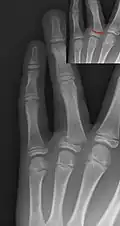

Salter–Harris I fracture of distal radius. -

Salter–Harris II fracture of ring finger proximal phalanx. -